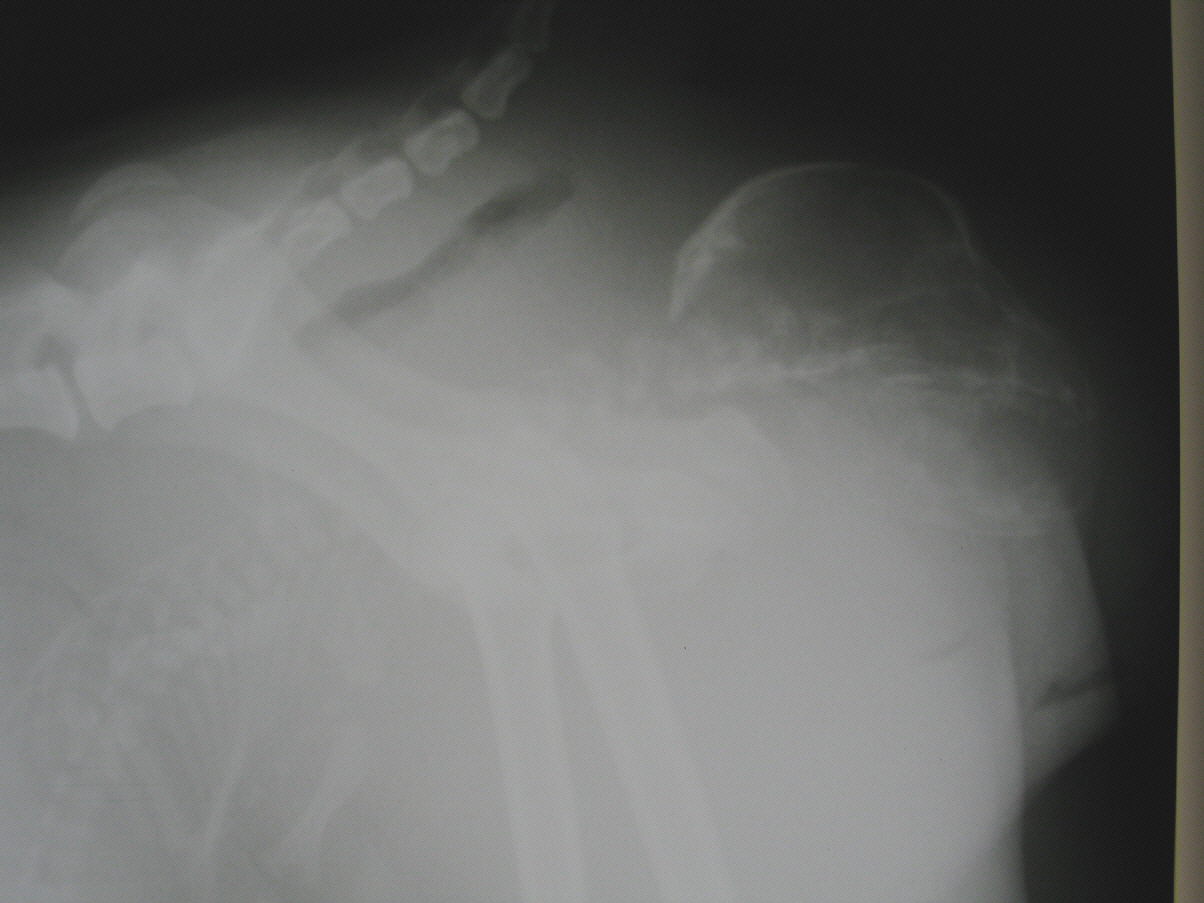

- Verlaufsuntersuchungen zur Trächtigkeit mit Ultraschall- und Röntgendiagnostik